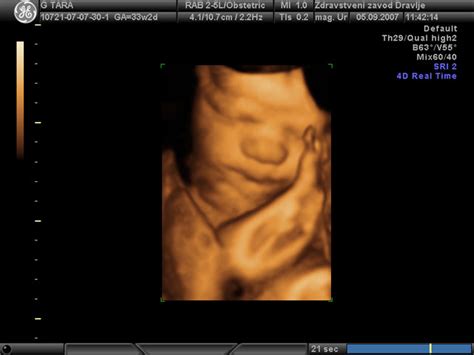

Zaskrbljenost glede rasti ploda med nosečnostjo je povsem naravna, še posebej, ko se pojavijo odstopanja v ultrazvočnih meritvah. V zadnjem trimesečju nosečnosti je natančno spremljanje rasti ploda ključnega pomena, saj lahko nepravilnosti v tem obdobju signalizirajo morebitne težave. V Sloveniji se je po osamosvojitvi spremenila zakonodaja glede spremljanja nosečnosti, kar je slovenskih nosečnicam odvzelo pravico do rutinskega tretjega kontrolnega ultrazvoka okoli 32. tedna nosečnosti, ki je bil v prejšnji državi obvezen. Trenutno zdravstvena politika v Sloveniji meni, da je rast ploda mogoče ustrezno spremljati s centimetrskim trakom, s katerim se meri razdalja med sramnično kostjo in vrhom maternice. Kljub temu večina nosečnic želi natančnejši nadzor nad nosečnostjo. Kontrola rasti ploda se lahko opravi kadarkoli, vendar se nepravilnosti najpogosteje ugotovijo po 26. tednu nosečnosti. V takih primerih je smiselno preveriti tudi pretoke v popkovnični arteriji, srednji možganski arteriji in materničnih arterijah. Rast ploda se običajno preverja na 14 do 21 dni, idealno pa na istem ultrazvočnem aparatu in pri istem preiskovalcu, saj to zmanjša odstopanja pri meritvah in omogoča natančnejšo oceno stanja ploda.

V primeru odstopanj v meritvah, kot je velikost glave, se lahko pojavi vprašanje, ali gre za napako pri merjenju ali za resničen zastoj v rasti. Pri tem je pomembno upoštevati, da živi plod ne "skrči", zato je verjetnost napake v meritvah pri eni od meritev glave, bodisi pri drugem ali tretjem ultrazvočnem pregledu, dokaj visoka. Na primer, če primerjamo meritve ploda pri 36. tednu nosečnosti (Glavni premer BPD = 82,1 mm, obseg glave HC = 283 mm, obseg trebuha AC = 312 mm, dolžina stegnenice FL = 74,9 mm) z meritvami pri 33. tednu nosečnosti (BPD = 81,7 mm, HC = 310 mm, AC = 291 mm, FL = 66,5 mm) in še starejšimi meritvami pri 21. tednu (BPD = 48 mm, HC = 186 mm, FL = 36 mm), lahko opazimo neskladja, ki nakazujejo na možnost napake pri merjenju.